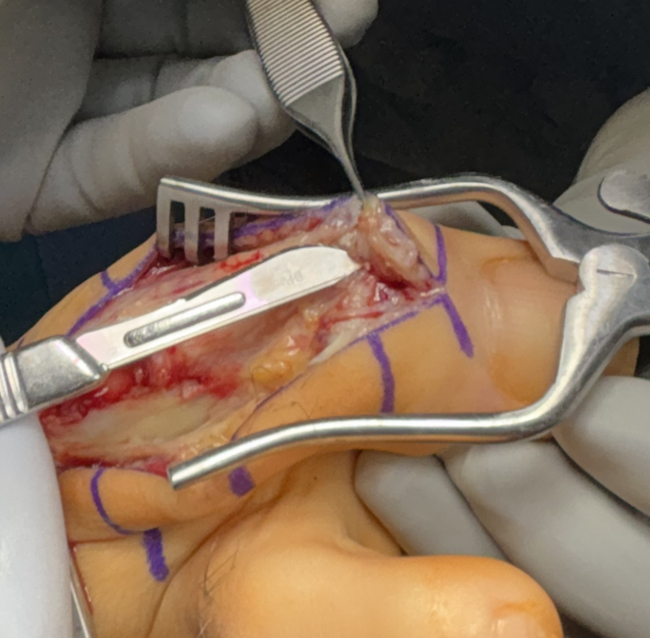

Our linear incision began dorsal and medial to the extensor tendon, one centimeter distal to the hallux interphalangeal joint and extending a centimeter proximal to the head of the first metatarsal. Using blunt and sharp dissection, we carried the incision down deep to bone. Using sharp dissection, we then reflected the joint capsule and soft tissues away from the hallux interphalangeal joint and the first metatarsal phalangeal joint. Using a sagittal saw, we resected the head of the first metatarsal at the neck, and passed it from the surgical field. We then used a sagittal saw to resect the base of the hallux proximal phalanx, and also passed it from the surgical field. Both sections of resected bone were sent for gross pathology, culture and sensitivity testing. Using sharp dissection, we excised the sesamoid complex in its entirety. Pulse lavage thoroughly irrigated the area.

Attention was then directed to the hallux interphalangeal joint where we noted chalky white-yellow deposits, a sample of which we sent for crystal analysis. Using a sagittal saw, we resected the head of the proximal phalanx was resected at the neck and the base of the distal phalanx, which we passed from the surgical field. Both of these additional sections of resected bone were sent for gross pathology, culture and sensitivity testing. Pulse lavage again thoroughly irrigated the site.

Following complete surgical debridement of infected and gout-involved bone and soft tissue, we directed our attention to reconstructing both of the joint spaces and restoring balanced tendon mechanics. To achieve this, we fashioned a biologic spacer by interposing slips of the patient’s native flexor and extensor tendons into the prepared joint space. We rolled the tendon tissue secured it centrally within the defect, providing a soft-tissue buffer that preserved anatomic spacing while mitigating direct osseous contact. The residual ends of the flexor and extensor tendons were then tensioned and anchored to opposing sides of the joint to recreate a physiologic agonist–antagonist relationship. This construct was designed to maintain reciprocal length–tension dynamics during motion, potentially enhancing proprioceptive signaling and soft-tissue balance across the reconstructed site. Resorbable antibiotic loaded cement beads (Stimulan Rapid Cure) were then prepared according to the manufacture’s recommendations using vancomycin and gentamicin and implanted into the space. The joint was ranged intraoperatively to confirm smooth excursion and absence of impingement before layered closure. The incision was then closed with layered sutures and the right hallux was splinted in a rectus slightly dorsiflexed position with sterile dressings. The patient was offloaded in a cast boot.